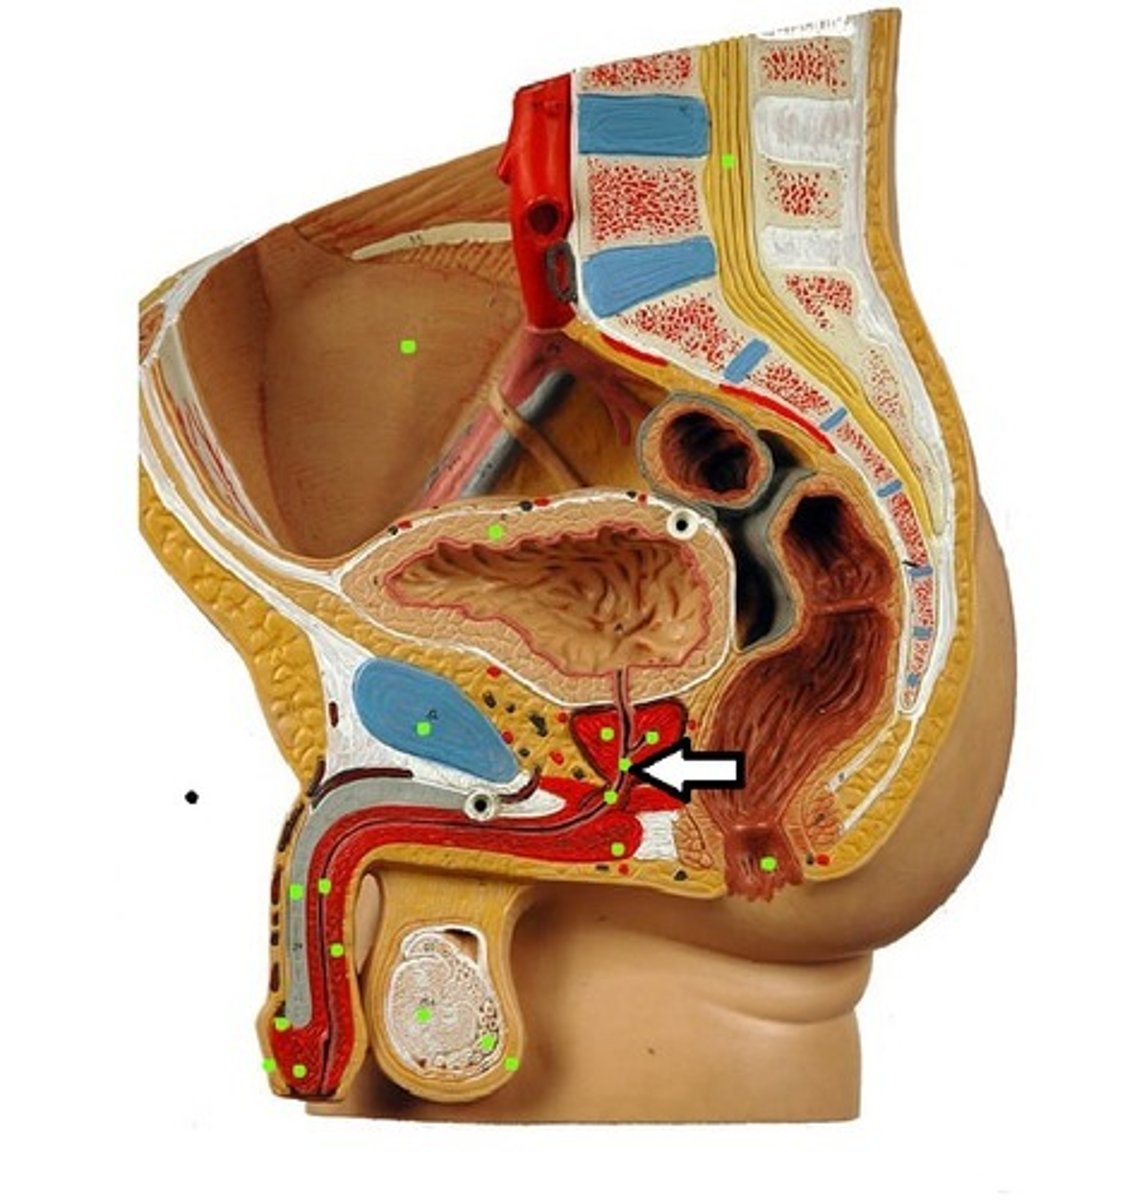

Prostate Gland

Seminal Vesicle

Ampulla of Ductus Deferens

Ejaculatory Duct leading to the Prostatic Urethra

ejaculatory duct

prostatic urethra

membranous urethra

bulbourethral gland